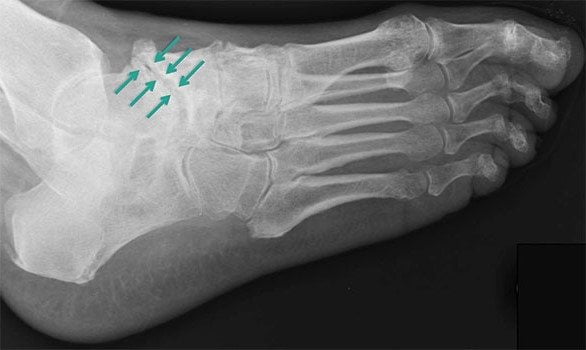

Третья стадия характеризуется сильной, нестерпимой болью, которая не проходит даже в состоянии покоя. Она распространяется на расположенные вблизи ткани, поэтому определить место локализации основного болевого очага сложно. На снимке хорошо визуализируется полное разрушение хряща и сильное уменьшение межкостного просвета. В этой стадии заболеванию присуща хроническая форма.

- деформация свода стопы, формирование остеофитов;

- рентгенография. Показывает состояние костно-суставных структур, определяет малейшие изменения в таранно-пяточном суставе;